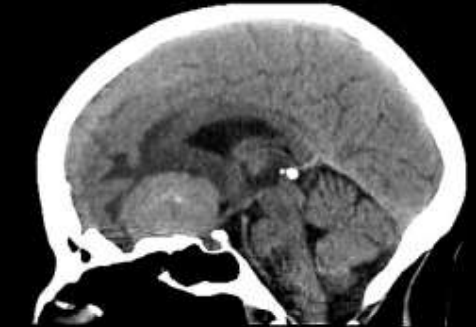

Na imagem abaixo é possível identificar uma lesão expansiva intracraniana sendo a causa provável um meningioma.

Assinale a alternativa correta acerca da classificação topográfica desta lesão.

Provas